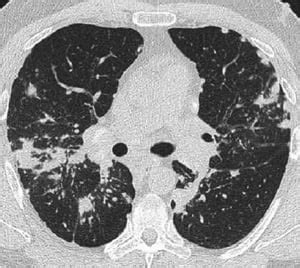

- Tomografia Computerizzata (TC) del Torace: Una TC ad alta risoluzione (HRCT) è più sensibile della RX nel identificare linfoadenopatia ilare e mediastinica, nonché anomalie parenchimali. I reperti tipici alla TC includono l'ispessimento dei fasci broncovascolari e delle pareti bronchiali, la bordatura dei setti interlobulari, opacità a vetro smerigliato, noduli, cisti o cavità parenchimali e bronchiectasie da trazione.

La TC può evidenziare diverse fasi della malattia:

- Stadio I: Adenopatia ilare bilaterale.

- Stadio II: Adenopatie ilari bilaterali con opacità interstiziali.

- Stadio III: Opacità interstiziali diffuse senza adenopatia ilare.

- Stadio IV: Grave fibrosi diffusa con alterazioni cistiche, spesso nei lobi superiori.

La TC può mostrare anche pattern atipici, come il "Galaxy sign" (un nodulo irregolare circondato da numerosi piccoli noduli) o un aspetto miliare con opacità a vetro smerigliato diffuse.